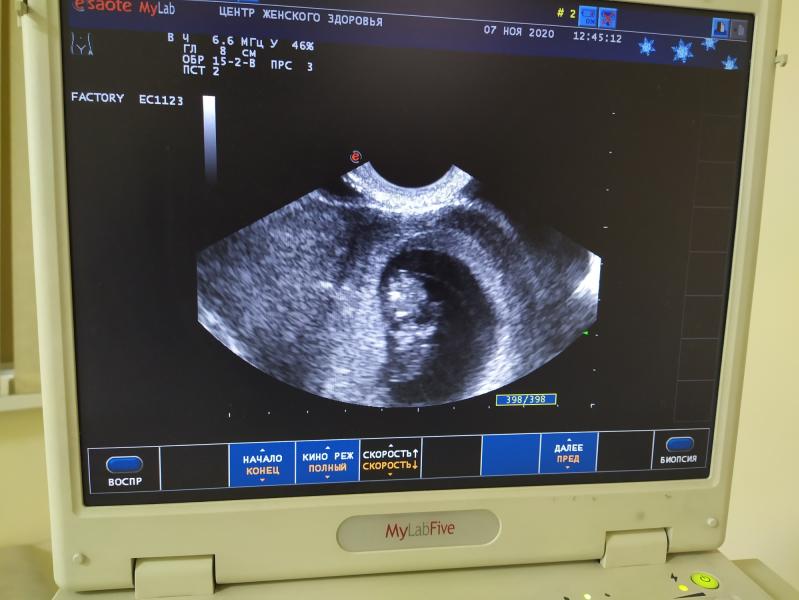

Девочки хочу поделится своими переживаниями.. Я готовлюсь третий раз стать мамой .. Вот пошла я на узи , в 10 недель беременности... Мне показали как движется малыш на этом сроке ... У него есть ручки и ножки ... Он активный...так быстро двигается просто я еще не слышу эго движения на этом сроке !! Я не знала (даже будучи уже мамой двоих деток ) что в этом периоде плод уже такой большой...

Да, да) помню на первом скрининге очень удивилась, увидев полноценного человечка! В моем представлении там плавал ещё головастик 😂

@lilek-vasilek да , я тоже именно так думала , что там головастик один 😉😅